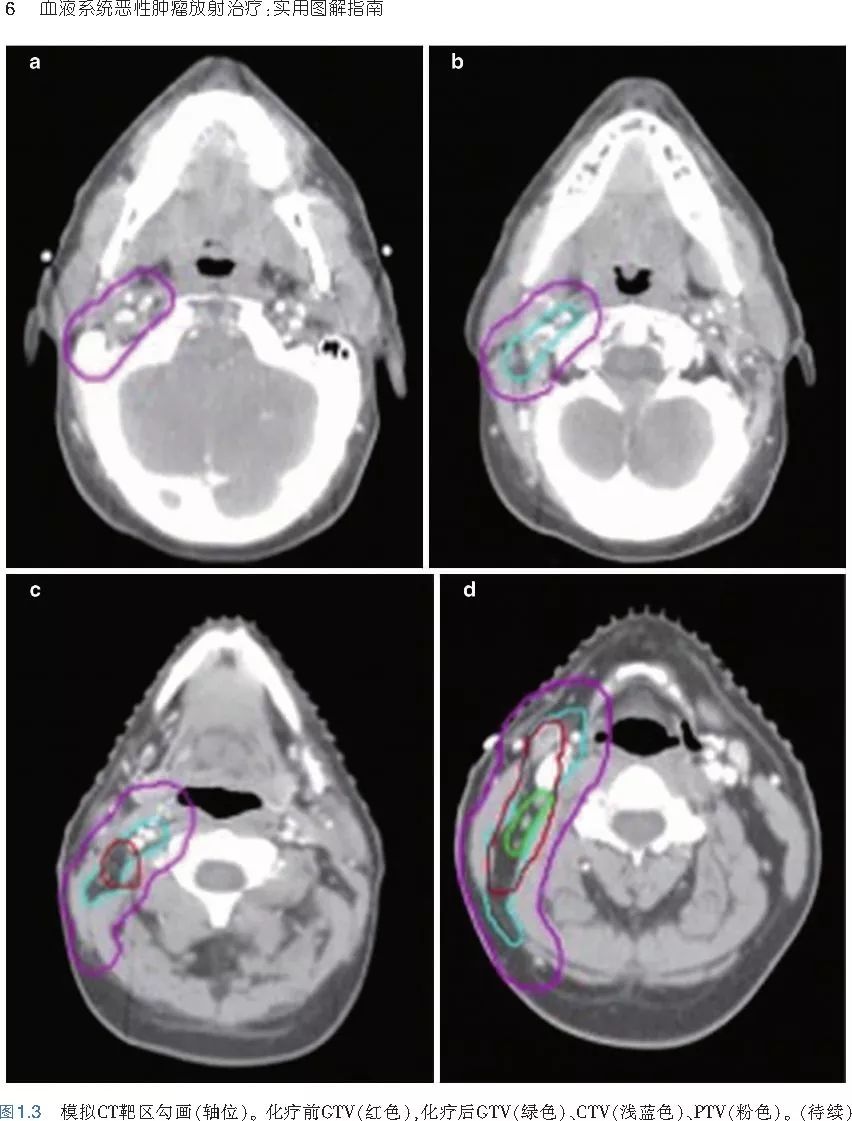

本书旨在帮助临床医生对常见血液系统恶性肿瘤疑难病例进行管理,包括霍奇金淋巴瘤、非霍奇金淋巴瘤和白血病患者,并通过多个病例进行阐述。案例讨论遵循标准格式,包括临床描述,其次是与诊断相关的病理描述和分期,然后详细讨论治疗选择。最后,确定治疗方案,并提供所使用的规划放疗技术/方式的图像。对放射肿瘤医生进行临床决策非常有帮助,针对血液病临床医生也有很好的指导作用。

近年来,放射治疗技术得到了迅速发展,调强放疗、图像引导放疗及其他新技术方法等,对恶性肿瘤治疗产生了巨大影响。现代放疗技术使精确定位、靶区勾画及给量成为可能,实现了肿瘤局控率和生活质量的双赢,对血液系统恶性肿瘤的临床治疗也产生了一定的影响。此书内容上不仅反映了血液系统恶性肿瘤综合治疗的进步,更是对其中放射治疗的新变化进行了系统、详细的阐述,这对当前血液系统恶性肿瘤放射治疗临床实践具有非常好的指导作用和参考价值。